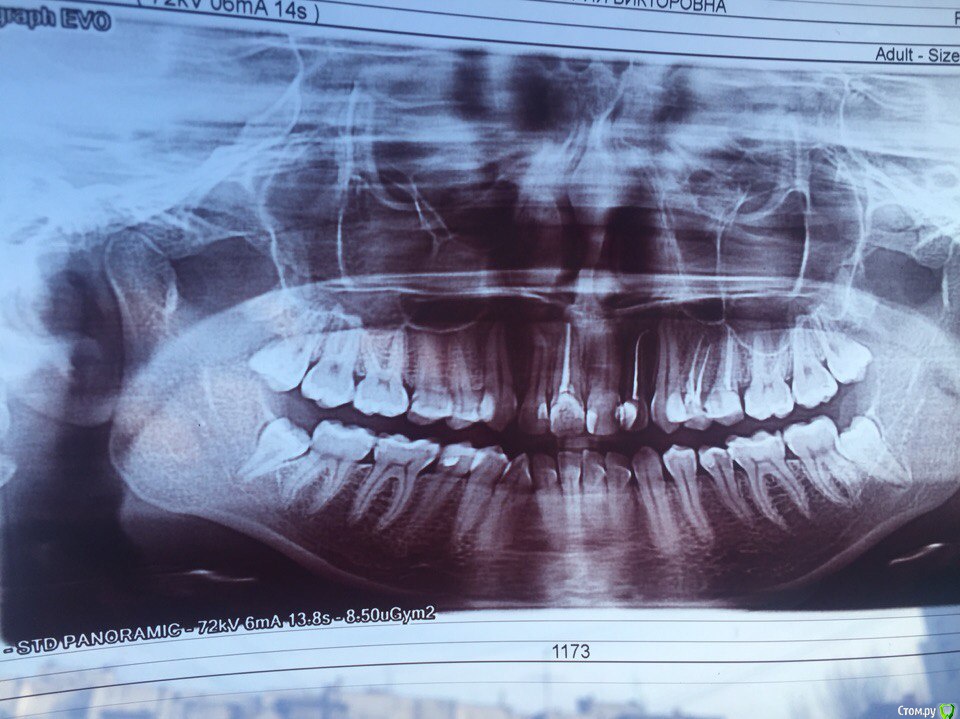

установка брекетов, удаление четырех четверок, требуется консультация

Здравствуйте! Мне 23 года, хотела бы получить консультацию. Одним ортодонтом мне было предложено удалить четыре четверки с последующем ношением брекетов в течение 1,5 лет. Другой доктор сказал, что можно удалить только по одной четверке слева вверху и внизу. В связи с этим подскажите, пожалуйста, какие зубы мне действительно стоит удалять и какова вероятность получения хорошего результата? и обязательно ли исправлять оба зубных ряда, так как дискомфорт мне доставляет по большей части только верхний ряд. в верхнем ряду у меня 4 мертвых зуба, в том числе одна четверка.

информация не вся (многое в клинике в кресле смотрится )

но  по этим данным я бы ничего (кроме восьмерок) не удаляла.